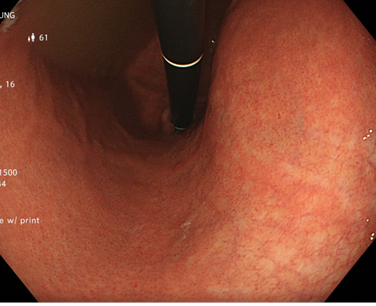

Kết quả nội soi đại tràng: có 3 polyp đại tràng (Paris Is, Kudo IIIL) (đã được cắt polyp qua nội soi), đại tràng sigmoid đã cắt một phần, tổn thương lồi đại trực tràng dạng polyp không cuống, ranh giới rõ, bề mặt màu hồng, có nhiều polyp có lớp nhầy ở trên bề mặt và thấy có hình ảnh da gà xung quanh tổn thương. Trên hình ảnh M-NBI thấy các tổn thương có các tuyến giãn nhẹ nhưng còn đều, mạch máu giãn nhẹ, chưa có biến đổi hình dạng --> đã tiến hành sinh thiết

Hình 2: Hình ảnh nội soi đại tràng

Tổn thương trên nội soi là hình ảnh các tổn thương lồi tại đại trực tràng dạng polyp không cuống, ranh giới rõ, bề mặt màu hồng, có nhiều polyp có lớp nhầy ở trên bề mặt. Chúng tôi nghĩ đến đây là hình ảnh của đa polyp mũ đại tràng mặc dù kết quả mô bệnh học chỉ kết luận là tổn thương viêm trợt mạn tính đang hoạt động, tạo hình ảnh giả polyp. Do trước đó cô ấy đã trải qua nhiều phương pháp điều trị theo hướng viêm ruột như kháng sinh Tinidazol, Levofloxacin, mesalazine… nhưng tình trạng đại tiện nhiều lần không được cải thiện, cùng với đó chúng tôi ghi nhận thấy có sự hiện diện của vi khuẩn H.pylori ở dạ dày. Vì vậy chúng tôi đã quyết định điều trị diệt trừ vi khuẩn H.pylori bằng phác đồ 4 thuốc: Tetracyclin 2g/ngày, Tinidazol 1,5g/ngày, Esomeprazol 80 mg/ngày, Bismuth 480 mg/ngày, thời gian điều trị là 2 tuần.